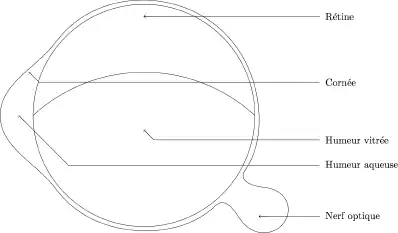

Dosage du potassium dans l’humeur vitrée de l'œil

L’utilisation du dosage du potassium contenu dans l’humeur vitrée de l'œil date de plus de 25 ans. C’est une méthode utile mais qui, à elle seule, n’est guère plus précise que les signes cliniques. Cette méthode repose sur le principe suivant : lorsque l'organisme cesse son activité, les cellules de la paroi perdent leur semi-perméabilité et par conséquent libèrent une partie des ions qu'elles contiennent (notamment le potassium). Et plus le temps s'écoule plus la teneur en potassium augmente. Il ne peut pas y avoir de contamination possible par l'humeur vitrée, car celle-ci pour être translucide ne doit contenir que très peu d'ions. L'avantage essentiel de cette méthode est qu’elle est utilisable pendant quelques jours (jusqu'à une semaine) alors que les méthodes non biologiques ne le sont que pendant 24 à 48 heures maximum.

- Prélèvement : le prélèvement se fait au moyen d'une seringue munie d'une aiguille intramusculaire, dans l’angle externe de l’œil, par aspiration douce afin d’éviter toute contamination sanguine ou rétinienne. Il doit être effectué le plus précocement possible c'est-à-dire lors de la découverte du corps, avant sa mise en réfrigération.

- Dosage : par un laboratoire habitué (électrodes sélectives) après agitation et homogénéisation.

- Conservation : la technique reposant sur un dosage total d’ions dans un liquide biologique, les conditions de conservation n’ont pratiquement aucune influence sur les résultats.

Les scientifiques ont pu établir, la formule suivante basée sur plus de 200 étalonnages :

entre 18 et 20 °C,

étant le délai post-mortem exprimé en heures et la concentration de potassium dans l'humeur vitrée en . Cette formule est relativement imprécise, puisque son écart type atteint 9 heures. Cependant elle est assez simple à appliquer puisqu'il s'agit d'une fonction affine de la concentration en potassium. Il est préférable de disposer des résultats d'un étalonnage effectué en laboratoire, afin d'avoir une estimation du délai post-mortem plus précise que celle donnée par la formule. Dans des conditions expérimentales, l’écart type est plus faible. Le potassium provenant de la lyse cellulaire n’a pas un accroissement linéaire. La température est un facteur très important puisque le froid ralentit considérablement l’augmentation de la quantité de potassium présente dans l'humeur vitrée.